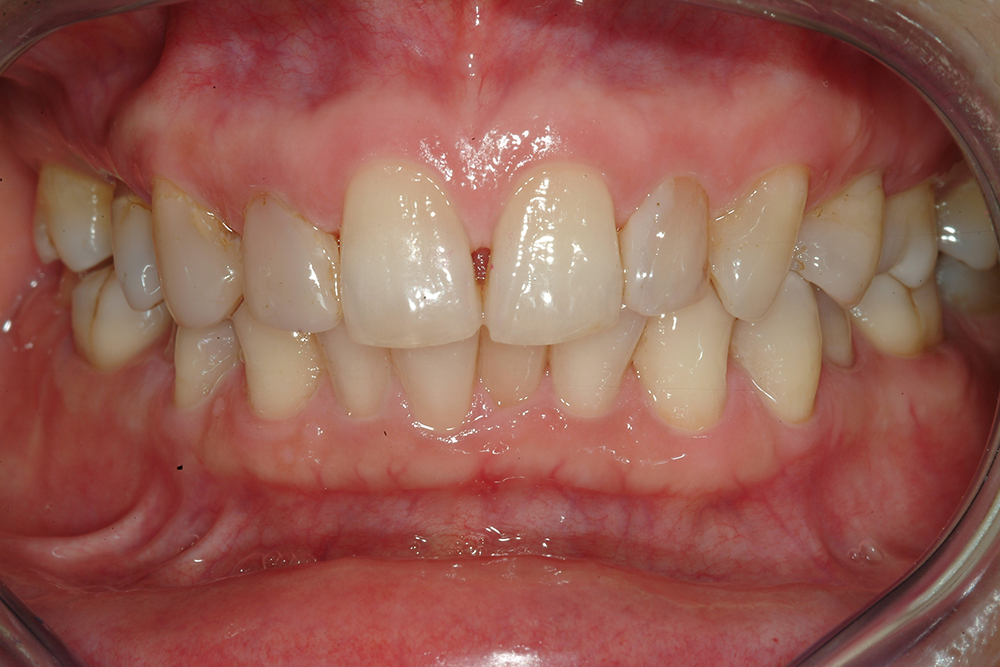

Cas 2

Dr Francesca Vailati – Alignement corrigé (ortho), dents blanchies, amélioration de l’état gingival